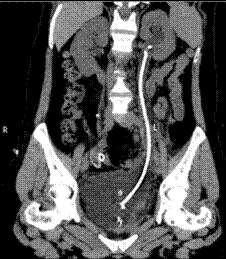

图一 术前泌尿系三维CT图二 术后3天泌尿系三维CT

在麻醉科和手术室的密切配合下,王春阳教授团队历时4小时,成功用6cm膀胱肌瓣替代了损伤的输尿管、留置输尿管支架完成手术。术中出血量仅20mL,术后连续观察三天没有再发生漏尿情况,患者顺利出院,出院3个月后引流管顺利拔除,仍无漏尿再发,治疗效果受到患者及家属高度认可。